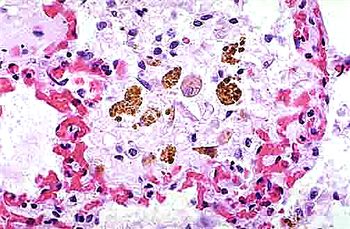

小鼠肺泡巨噬細(xì)胞的應(yīng)用

巨噬細(xì)胞,作為免疫系統(tǒng)中的重要成員,以其獨(dú)特的吞噬能力和廣泛的生物學(xué)功能,在機(jī)體的免疫防御、組織修復(fù)、炎癥反應(yīng)調(diào)控等方面發(fā)揮著至關(guān)重要的作用。

吞噬作用 巨噬細(xì)胞最顯著的功能是其強(qiáng)大的吞噬能力。它們能夠伸出偽足包圍并吞噬細(xì)菌、衰老細(xì)胞、凋亡細(xì)胞、細(xì)胞碎片及病原體等,形成噬體或吞噬小泡,隨后將其消化分解。這一過程不僅有助于清除體內(nèi)的有害物質(zhì),還能激活其他免疫細(xì)胞對(duì)病原體作出反應(yīng)。